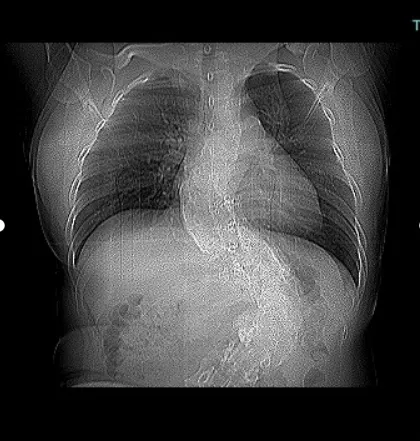

近日,滄州市中心醫(yī)院心血管內(nèi)五科為一名卵圓孔未閉(PFO)合并有脊柱側(cè)彎和后突畸形的患者成功進(jìn)行了卵圓孔未閉介入封堵術(shù),這是滄州市首例心腔內(nèi)超聲(ICE)引導(dǎo)下完成的PFO封堵術(shù)。

該患者有多年的頭痛病史,經(jīng)神經(jīng)內(nèi)科篩查考慮為PFO,并經(jīng)過規(guī)范藥物治療,效果不明顯,來PFO專病門診找到醫(yī)院心血管內(nèi)五科副主任牛和平,經(jīng)過仔細(xì)詢問病史,查看相關(guān)檢查結(jié)果,診斷PFO明確,考慮患者有介入封堵的指征,而后收入院。但患者患有先天脊柱側(cè)彎及后突,血管及心臟結(jié)構(gòu)有明顯轉(zhuǎn)位,常規(guī)超聲并不能完全準(zhǔn)確引導(dǎo)介入操作,為介入手術(shù)帶來極大的困難和風(fēng)險。醫(yī)院副院長、心血管內(nèi)五科主任張軍教授,副主任牛和平,副主任付金國,副主任醫(yī)師王磊,主治醫(yī)師于愷等反復(fù)討論,決定實施ICE指導(dǎo)下PFO介入封堵術(shù)。術(shù)中,在ICE的實時引導(dǎo)下,傳送鞘管順利進(jìn)入右心房,明確PFO的位置后導(dǎo)絲成功通過未閉卵圓孔進(jìn)入左房,之后順利植入封堵器,ICE實時確認(rèn)封堵術(shù)釋放位置良好,封堵效果極佳,手術(shù)時間不到半小時,患者恢復(fù)良好,目前已經(jīng)出院。